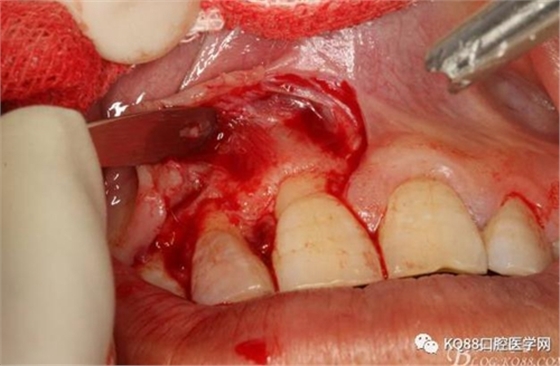

圖6.行唇側角形切口(11近中垂直切口+齦溝內水平切口)垂直切口距離前庭溝約1~2mm。這樣可以減輕術后腫脹。

圖7. 角形切口中的齦溝內切口情況:11號刀片伸進齦溝內斜切。

圖8.從垂直切口和水平切口的連接處翻瓣。發(fā)現(xiàn)11和12之間的骨壁有缺損。

圖9.翻開角形瓣后,有骨壁缺損,囊壁有穿孔,這就是溢膿的竇道出口。